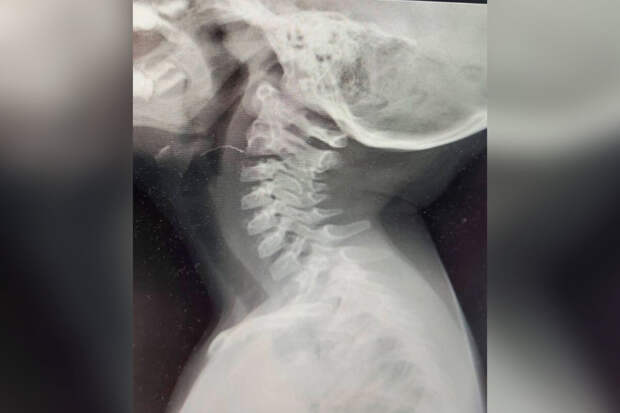

Врачи выяснили, что дискомфорт ребенку доставляла проволока длиной больше двух сантиметров.

С помощью эндоскопической техники они достали предмет.По словам специалистов, семья вовремя обратилась за помощью. Если бы они пришли в больницу позже, у пациентки могли появиться гнойные осложнения.